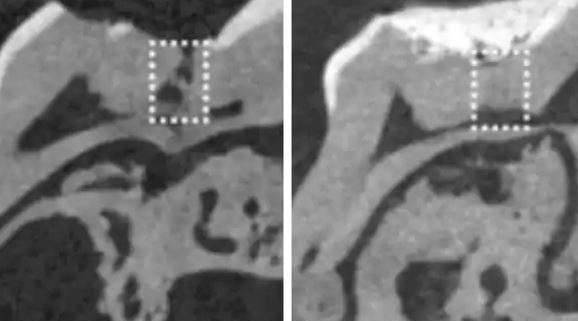

▼目前这项新技术还在实验当中,不过如果真的可行的话,大家还是逃不过必须钻牙的命运,因为医生必须先在牙齿钻出一个小洞孔,才可以把浸有药物的海绵塞入,让牙齿的细胞吸收,这样才可以打败可恶的蛀牙!